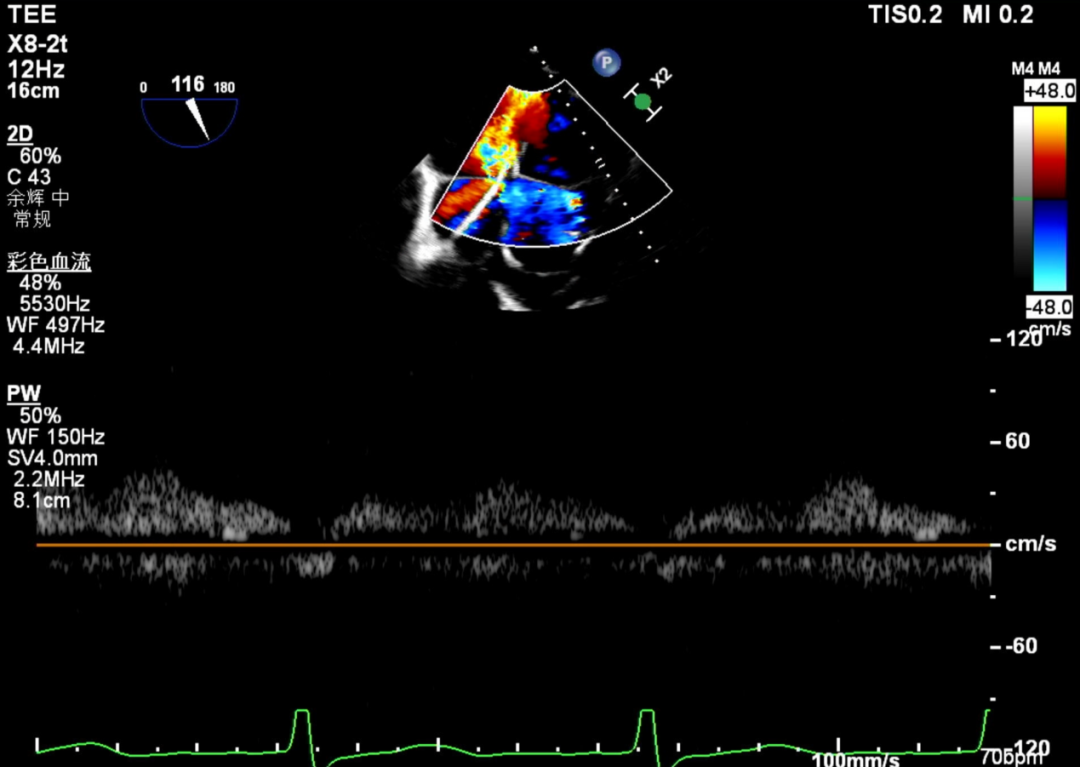

术前肺静脉频谱

怎么上穿刺鞘攻克巨大左房伴转位穿刺难关!温医大附一院周浩教授团队创新应用“导丝定位+可调弯鞘”技术完成高难度TEER手术_https://www.jmylbn.com_新闻资讯_第11张

1.二尖瓣重度关闭不全(4+),瓣环明显扩大(AP径4.6cm,LM径3.9cm),扁平,关闭时瓣叶对合不佳(carpentier I),1-3区均可见反流束,返流宽度达26mm;肺静脉频谱呈收缩期反向。

术后肺静脉频谱